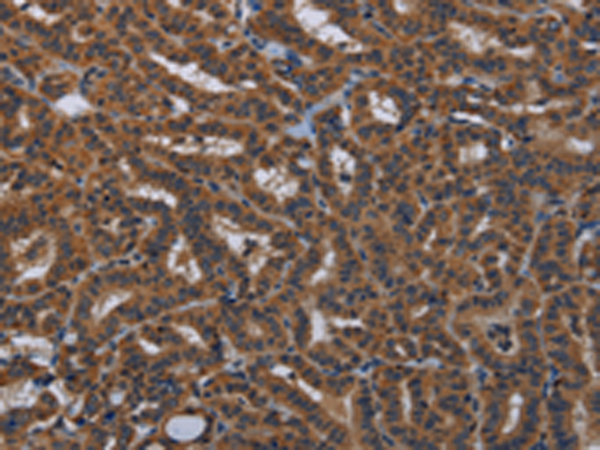

分类: 科研抗体货号: P08427别名: IDH; IDP; IDHM; IDPM; ICD-M; D2HGA2; mNADP-IDH应用: WB,IHC反应种属: Human, Mouse, Rat